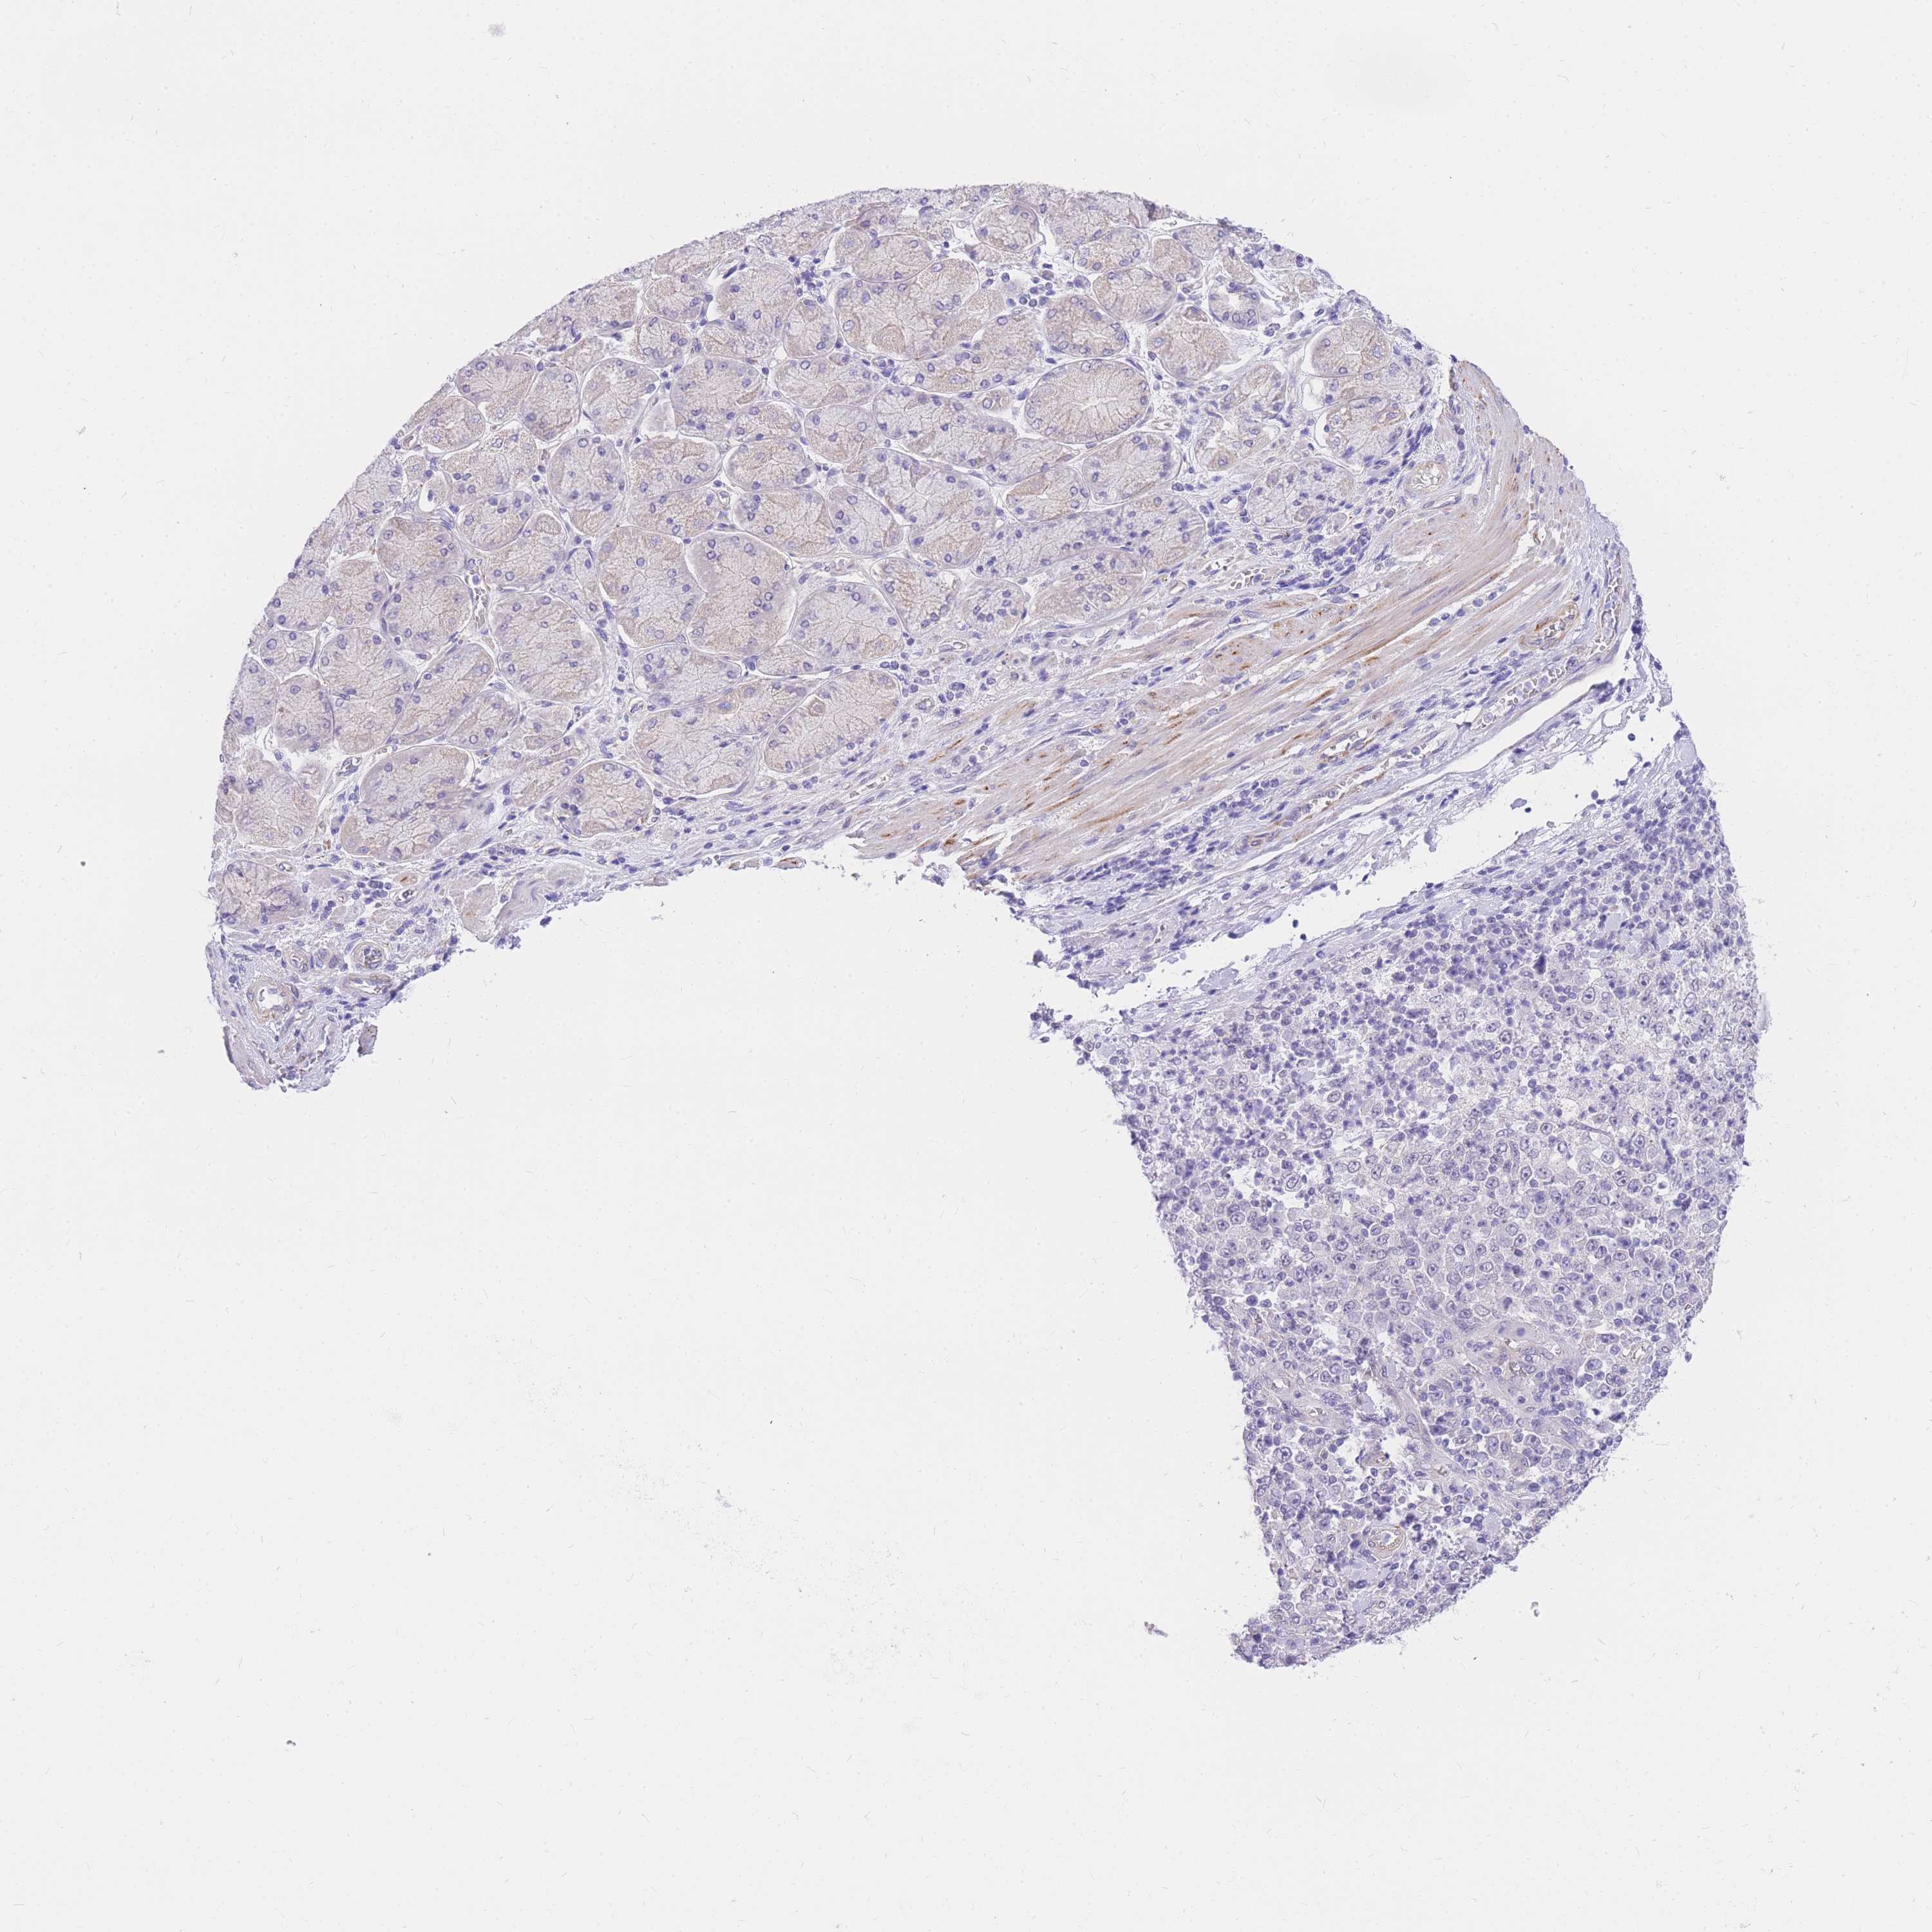

STOMACH CANCER - Protein expressioni

A mouse-over function shows sample information and annotation data. Click on an image to view it in a full screen mode. Samples can be filtered based on level of antibody staining by selecting one or several of the following categories: high, medium, low and not detected. The assay and annotation is described here.

Note that samples used for immunohistochemistry by the Human Protein Atlas do not correspond to samples in the TCGA dataset.

Antibody stainingi

Antibody staining in the annotated cell types in the current human tissue is reported as not detected, low, medium, or high, based on conventional immunohistochemistry profiling in selected tissues. This score is based on the combination of the staining intensity and fraction of stained cells.

Each image is clickable and will lead to virtual microscopy that enables deeper exploration of all samples and also displays staining intensity scores, fraction scores and subcellular localization as well as patient and tissue information for each sample.

Antibody HPA027242

Antibody HPA027328

Staining

High

Medium

Low

Not detected

Intensity

Strong

Moderate

Weak

Negative

Quantity

>75%

75%-25%

<25%

None

Location

Nuclear

Cytoplasmic/membranous

Cytoplasmic/membranous,nuclear

Adenocarcinoma, NOS